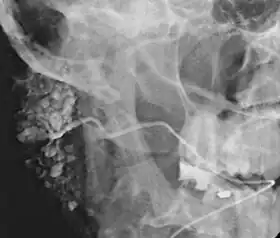

Sialogram in a patient suspected of Sjögren's syndrome

This procedure is indicated when there is recurrent swelling and pain on the face but ultrasound has not revealed any problems. If Sjögren syndrome (also known as Sicca syndrome, an autoimmune disease that affects the lacrimal and salivary glands, causing reduced tears and saliva production) is suspected, this procedure is useful. Besides, when interventional proecudre is planned such as stone removal from salivary ducts or dilatation of the strictures in the salivary gland, this procedure is also indicated.[4] However, for those who are pregnant, with allergy to iodinated contrast, and ongoing infection or inflammation of the face, the procedure is contraindicated.[4]

This study is interpreted by evaluating the morphology of the salivary ducts for obstructions and chronic inflammation. Sialodochitis is a term describing dilation of the ducts caused by repeated inflammatory or infective processes. There is also irregular salivary duct stricture (narrowing) of the duct, which creates an appearance known as "sausage link" pattern on a sialogram. Suggestions of abscesses and autoimmune diseases such as Sjögren syndrome can also be elicited. Sialadenitis is inflammation of the salivary glands, which may cause acinar atrophy and create an appearance known as "pruning of the tree" on a sialogram, where there are less branches visible from the duct system. A space occupying lesion that occurs within or adjacent to a salivary gland can displace the normal anatomy of the gland. This may create an appearance known as "ball in hand" on an sialogram, where the ducts are curved around the mass of the lesion.[6]